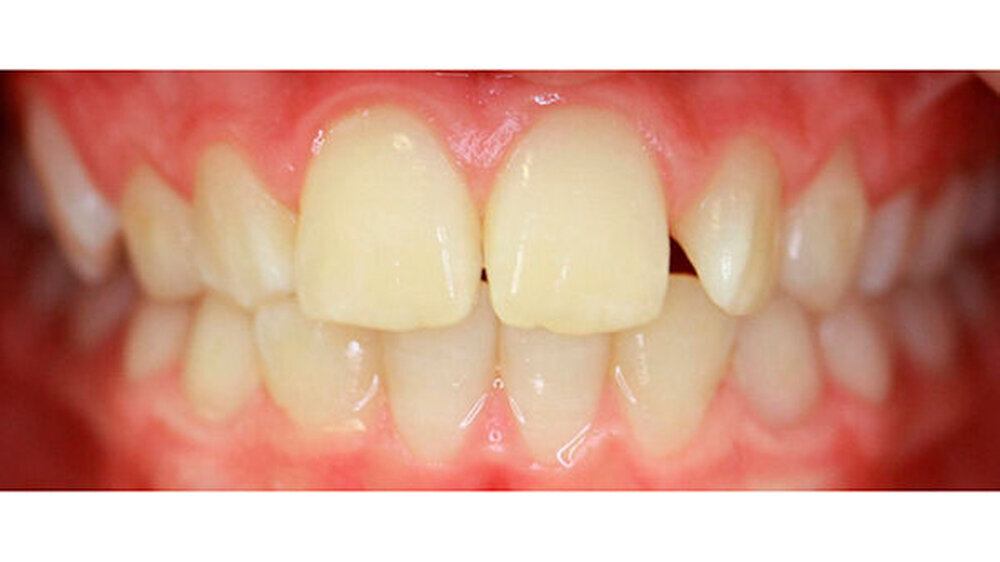

Nach dreijähriger kieferorthopädischer Behandlung konnte die Patientin entbändert werden. Eine Stabilisierungsphase mit herausnehmbaren Essixschienen folgte. Nach Ende der aktiven Behandlungszeit waren die Therapieziele weitgehend erfolgreich umgesetzt worden.

Bei dieser Patientin hätte man die Angulation von Zahn 14 den Torque von Zahn 13 noch etwas besser einstellen können. Die Patientin wünschte sich in der Finishingphase jedoch eine vorzeitige Entbänderung.